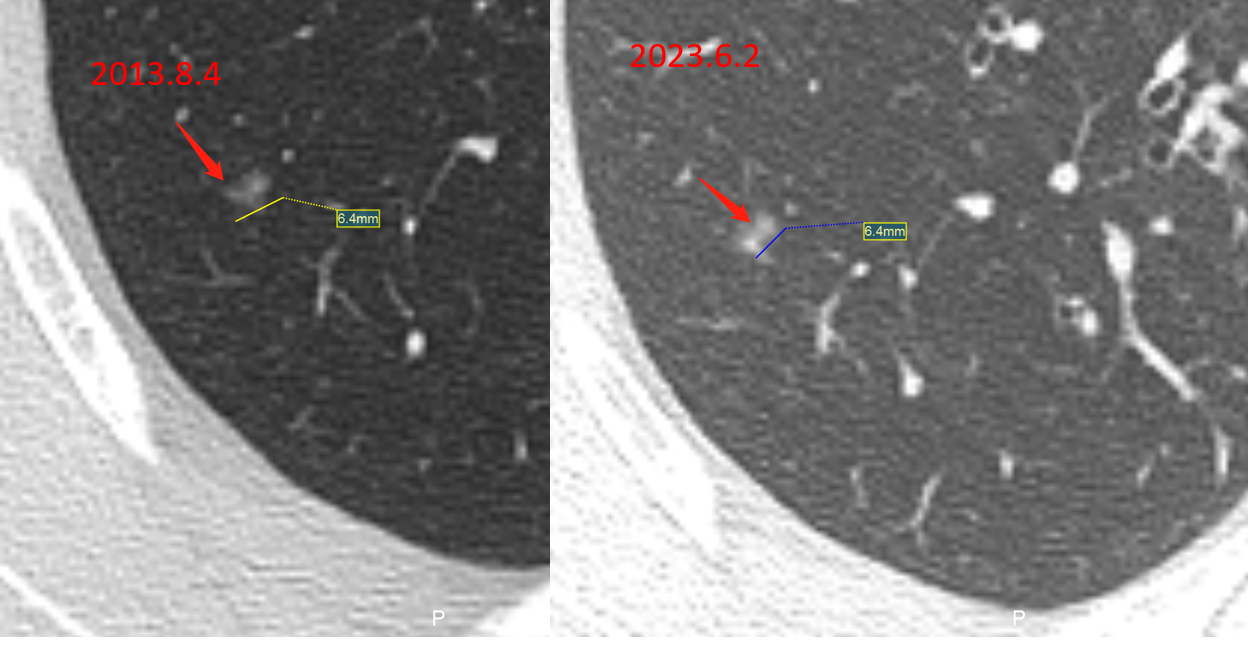

男性,56岁,2013年发现右肺上叶磨玻璃结节,直径约6mm,密度欠均匀.